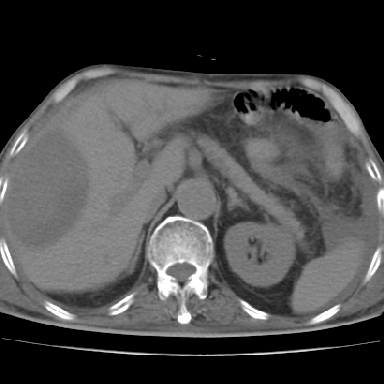

以下是引用qian在2006-12-4 19:11:00的发言:[br]胸腔和腹腔内均见有液性影,肝上极包膜下有一较大椭圆形低密度影,密度均匀,边缘清晰,结合病史考虑术后肝脓肿并胸腹腔积液。

以下是引用dyqct在2006-12-4 19:54:00的发言:[br]考虑:1、肝包膜下脓肿;[br] 2、少量腹水;[br] 3、右侧少量胸膜腔积液。